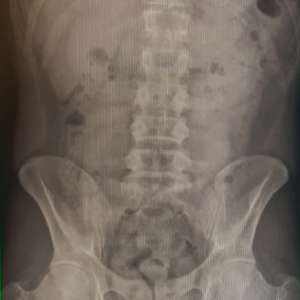

Chiar dacă, la controlul bagajelor nu au fost identificate droguri ascunse, pasagerul a fost examinat și cu aparatul X Ray din dotarea Poliției de Frontieră, fiind observate, în stomacul bărbatului, 18 caşete cu substanţă.